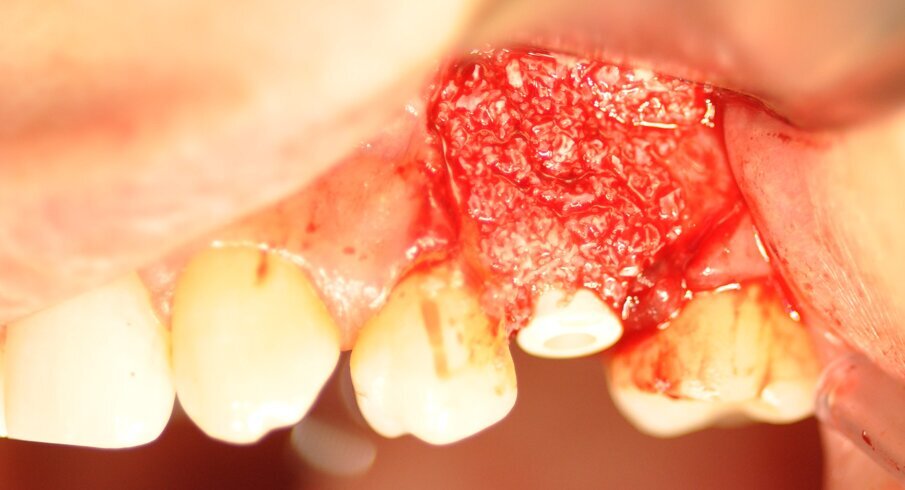

La paziente presentava un primo premolare superiore sinistro non recuperabile. La CBCT mostra la situazione iniziale (Fig. 1). Si noti quella che appare come una grande fenestrazione buccale nell’area della resezione radicolare (Fig. 2). Il dente fratturato è stato estratto (Figg. 3, 4). Lo scollamento del lembo di accesso rivela la fenestrazione buccale (Fig. 5). L’osteotomia è stata preparata secondo il protocollo di fresatura di Neoss ProActive Edge (Fig. 6). Successivamente viene posizionato un impianto Neoss ProActive Edge Ø 5.0 × 13 mm (Fig. 7). L’impianto è stato posizionato in una situazione di disponibilità ossea molto limitata e densità ossea media (Fig. 8). Nonostante le limitazioni dovute alla condizione ossea, è stata raggiunta una buona stabilità primaria. È stato utilizzato un torque di inserimento di 20 Ncm, l’ISQ è risultato in un range di 70/77. Per correggere la fenestrazione buccale è stato eseguito un innesto con particolato osseo di origine porcina (Fig. 9). L’innesto osseo è stato coperto con una membrana di collagene riassorbibile (Fig. 10). Il lembo mucoso è stato suturato attorno al pilastro di guarigione in PEEK, consentendo la guarigione in una sola fase (Fig. 11).